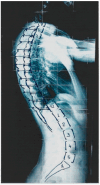

In this opinion article, there is an analysis and discussion regarding the effects of growth on the spinal and rib cage deformities, the role of the rib cage in scoliogeny, the lateral spinal profile in adolescent idiopathic scoliosis (AIS), the genetics and epigenetics of AIS, and the interesting and novel field investigating the sleep impact at nighttime on AIS in relation to the sequence of the scoliogenetic changes in scoliotics. The expressed opinions are mainly based on the published peer-reviewed research of the author and his team of co-authors. Based on the analysis noted above, it can be postulated that the vertebral growth changes in the spine during initial idiopathic scoliosis (IS) development are not primary-intrinsic but secondary changes. The primary cause starting the deformity is not located within the vertebral bodies. Instead, the deformations seen in the vertebral bodies are the secondary effects of asymmetrical loads exerted upon them, due to muscular loads, growth, and gravity.